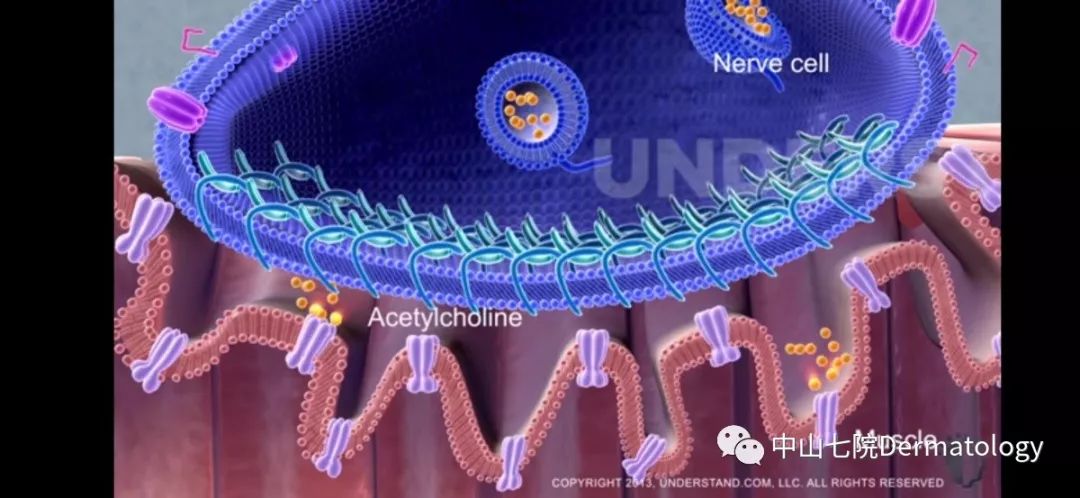

肌肉的收缩依赖的是神经的支配,简单来说,神经传递信号被肌肉接收即产生了肌肉收缩,而肉毒素恰恰阻断了这一信号的传递与接受过程,从而减弱了肌肉收缩,那些依赖肌肉收缩所产生的皱纹就被统统拿下了。

另外,肌肉长期得不到神经的信号就会萎缩变小,那些通过减少肌肉体积实现的轮廓塑性(瘦脸,瘦腿,瘦肩)就分分钟被get啦